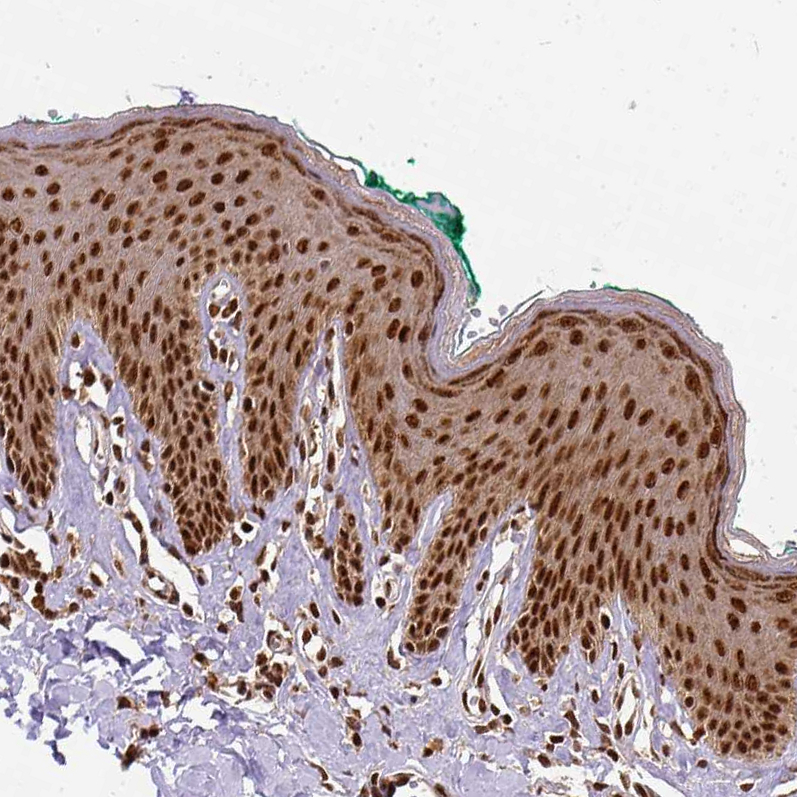

Immunohistochemical staining of human cerebral cortex, duodenum, skin and testis using Anti-NACC1 antibody HPA021238 (A) shows similar protein distribution across tissues to independent antibody HPA062245 (B).